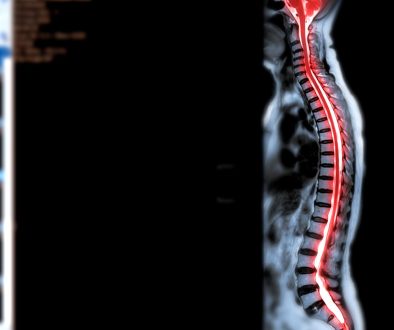

جراحة صمامات المخ تهدف في الأساس إلى معالجة مشاكل السائل النخاعي مثل استسقاء الرأس. يتم ذلك عن طريق زرع صمام يعمل على تصريف السائل النخاعي الزائد إلى أجزاء أخرى من الجسم حيث يمكن امتصاصه. القسطرة المخية تُستخدم لتوجيه الصمام بدقة ولتسهيل عملية التصريف.

قد تكون هناك حاجة لجراحة صمامات المخ إذا كان لديك استسقاء الرأس. هذا هو حالة يتم فيها تراكم السائل النخاعي في التجاويف داخل الدماغ، مما يؤدي إلى الضغط الزائد وظهور أعراض مثل الصداع، واضطرابات الرؤية، ومشاكل التوازن.

قبل أي إجراء جراحي، سيكون من الضروري القيام ببعض الفحوصات الطبية للتحقق من حالتك الصحية العامة. قد تشمل هذه الفحوصات تحاليل الدم، والتصوير بالرنين المغناطيسي أو الأشعة المقطعية.